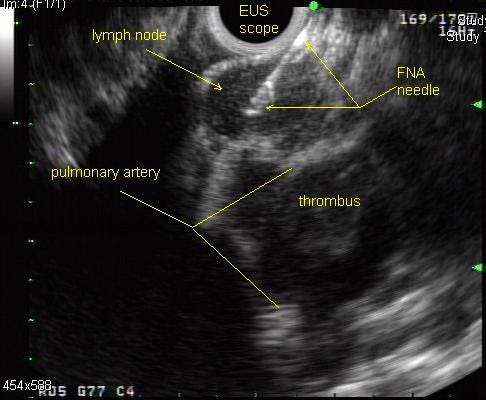

All got endoscopic ultrasound / endobronchial ultrasound with fine needle aspiration. 76 of the 83 had adequate samples. The main results: